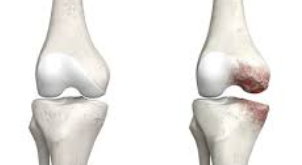

관절염과의 관계

무릎 연골 손상이 진행되면 결국 퇴행성 관절염으로 발전하게 됩니다. 초기 연골 손상 증상이 관절염의 전단계 증상으로 볼 수 있으며, 조기 발견과 치료가 관절염 예방에 매우 중요합니다.